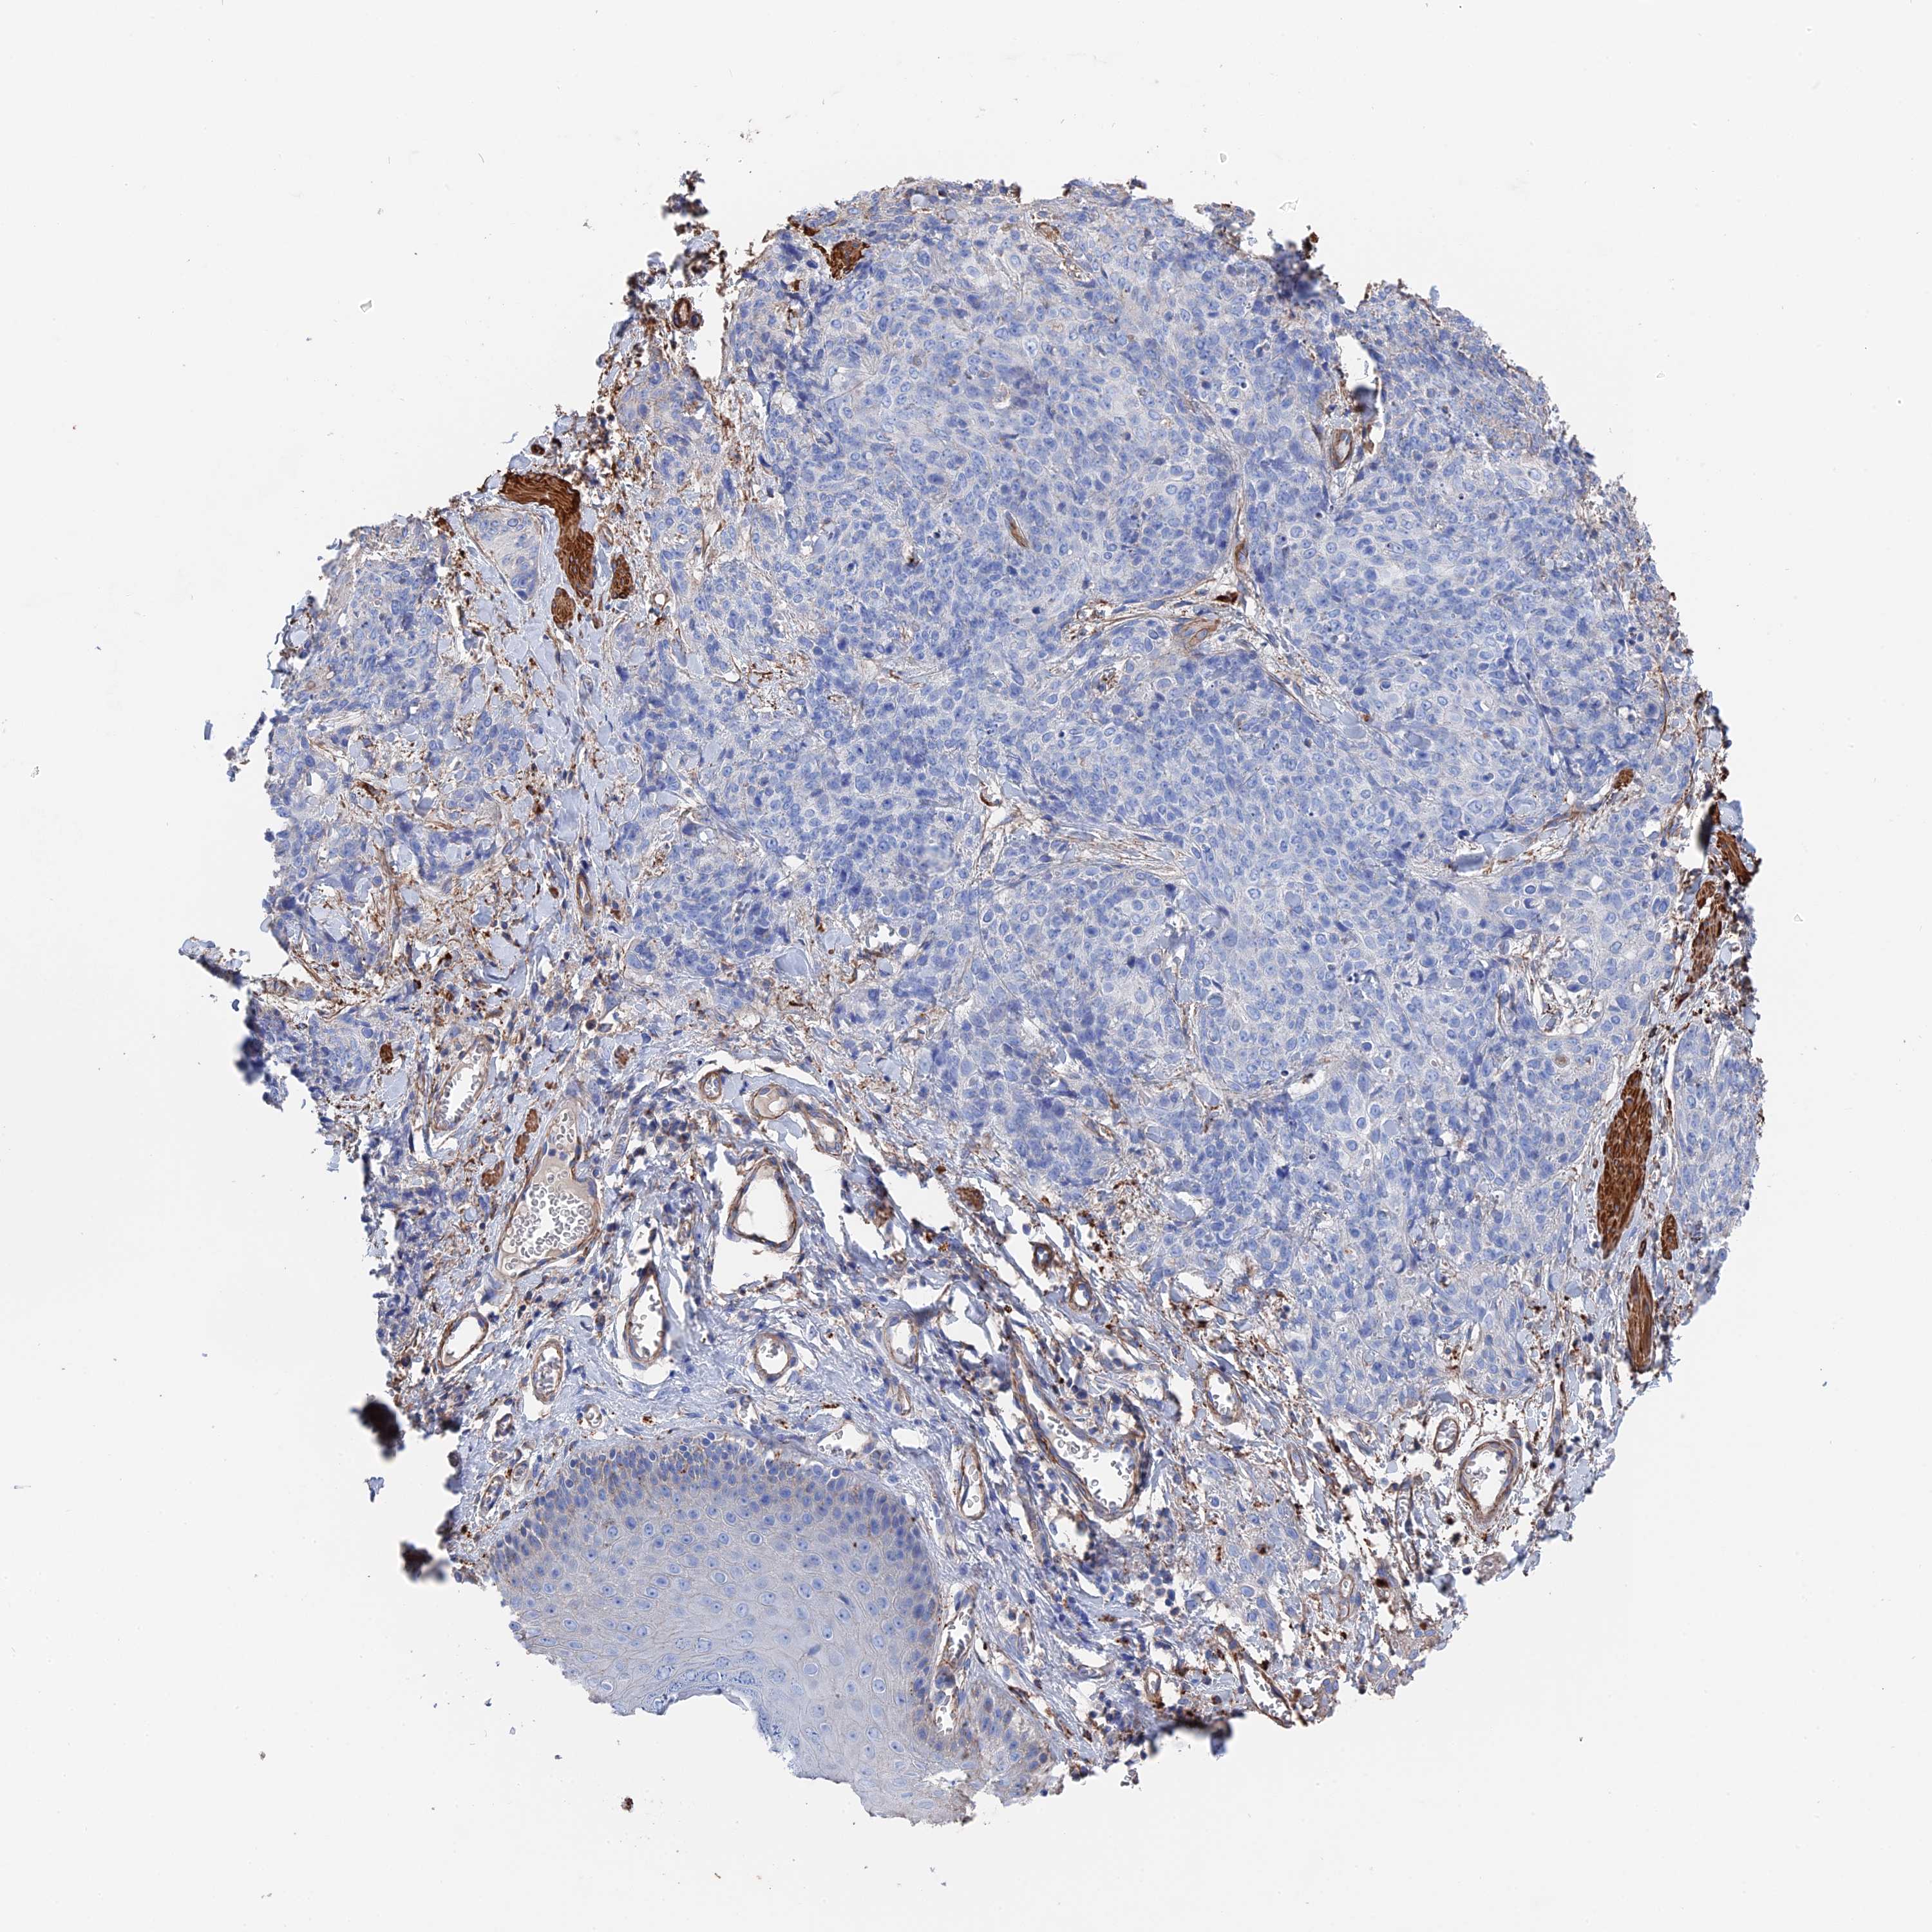

Antibody HPA040839

Staining

Low

Intensity

Weak

Quantity

75%-25%

Location

Cytoplasmic/membranous

Squamous cell carcinoma, NOS